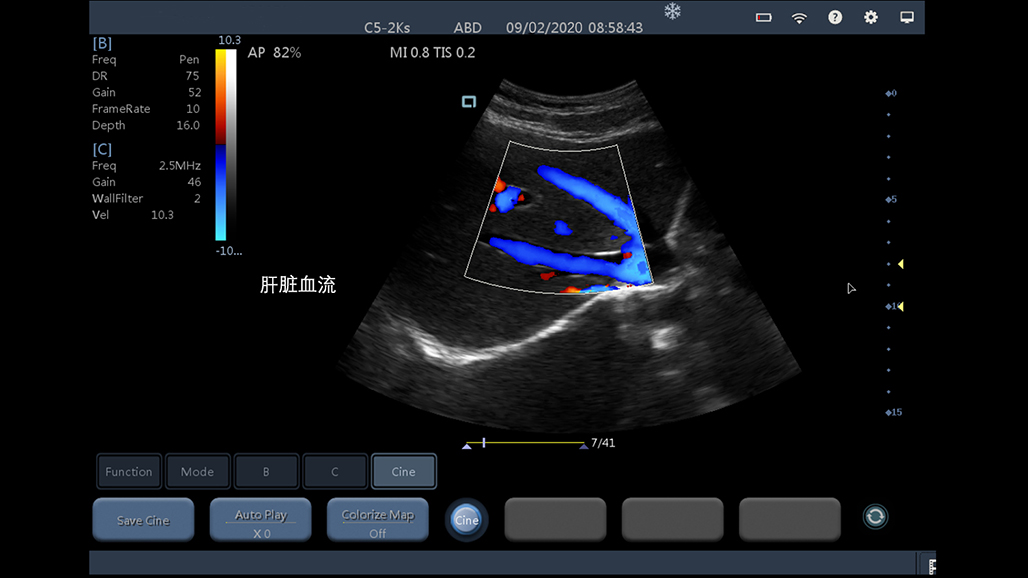

• 大凸

腹部

肾脏

妇科产科

心脏

肺等